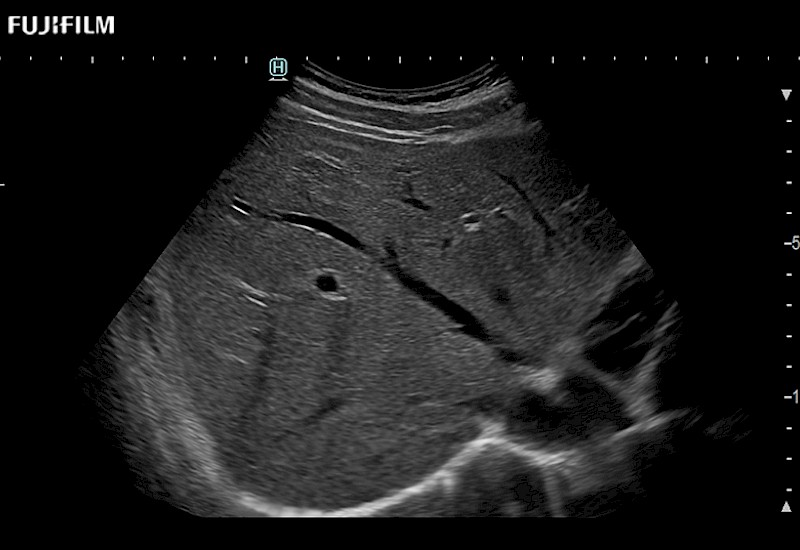

Extraordinary high-resolution digital imaging

- Exceptional near and far-field resolution

- Instant feedback on tumor margin delineation

- Valuable information to guide tumor resections

- Exceptional near and far-field resolution

- Instant feedback on tumor margin delineation

- Exceptional near and far-field resolution

- Exceptional near and far-field resolution

- Instant feedback on tumor margin delineation

- Exceptional near and far-field resolution

- Instant feedback on tumor margin delineation

- Exceptional near and far-field resolution

- Instant feedback on tumor margin delineation

- Exceptional near and far-field resolution

- Instant feedback on tumor margin delineation

- Valuable information to guide tumor resections

- Exceptional near and far-field resolution

- Instant feedback on tumor margin delineation

- Valuable information to guide tumor resections

- Exceptional near and far field resolution

- Instant feedback on tumor margin delineation

- Valuable information to guide tumor resections

- Exceptional near and far-field resolution

- Instant feedback on tumor margin delineation

- Valuable information to guide tumor resections

- Exceptional near and far field resolution

- Instant feedback on tumor margin delineation